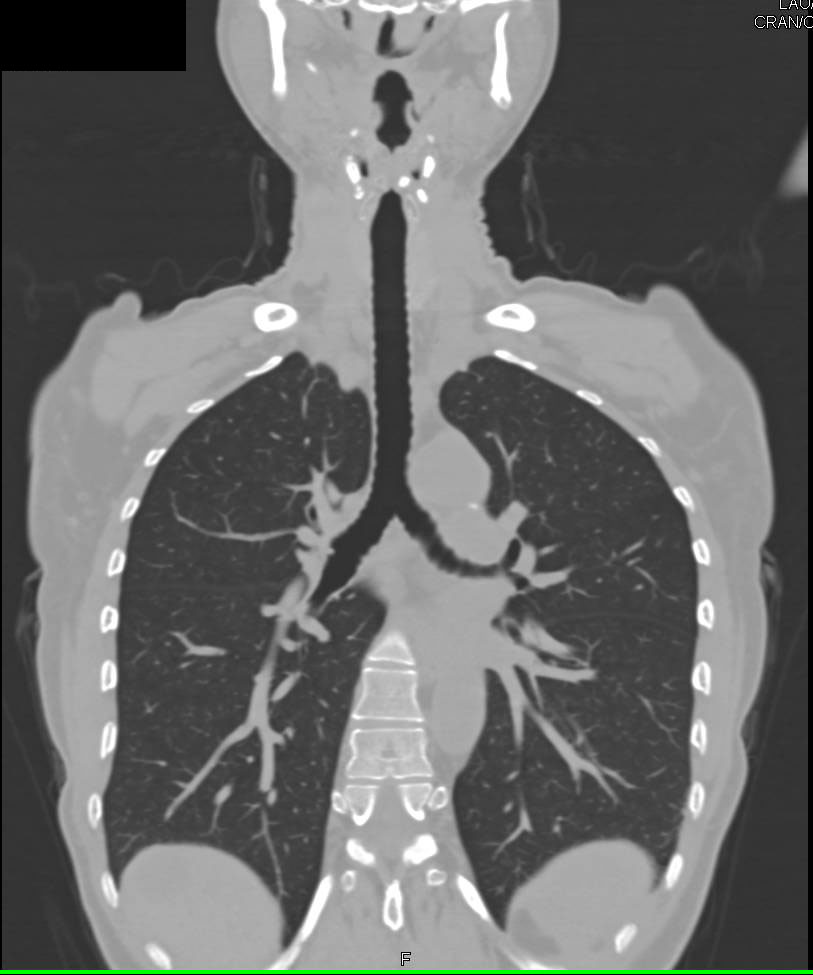

Ulcerating Plaque in Descending Thoracic Aorta and Thrombus in Arch